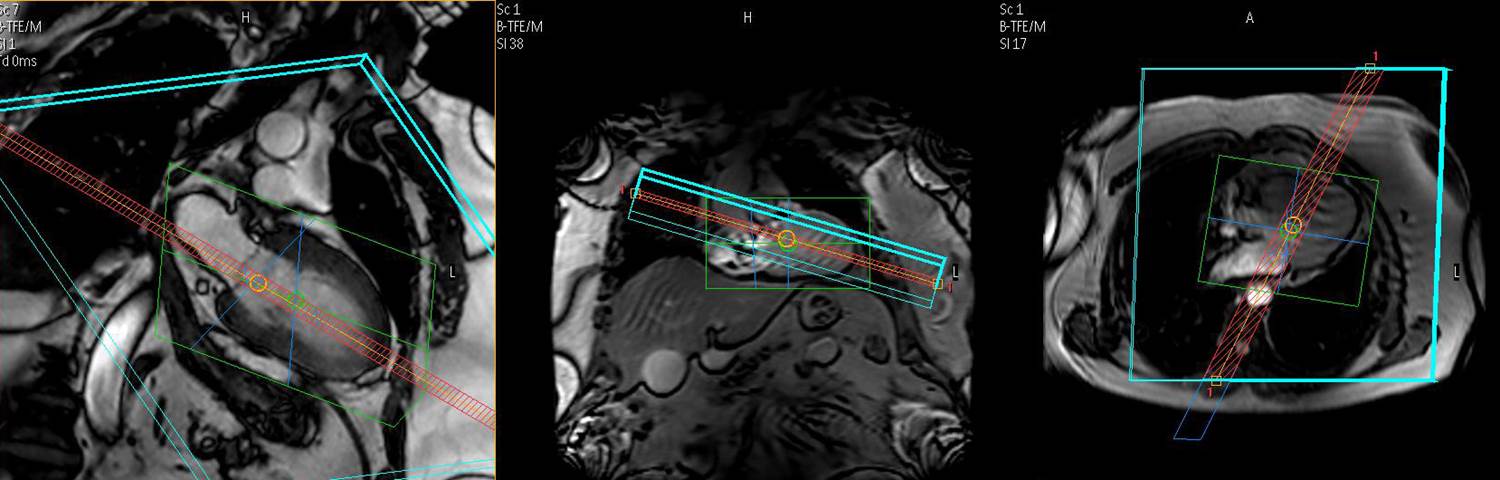

125. Jahnke C, Nehrke K, Paetsch I, Schnackenburg B, Gebker R, Fleck E, Nagel E. Improved bulk myocardial motion suppression for navigator-gated coronary magnetic resonance imaging. J Magn Reson Imaging. 2007; 26:780-786.

116. Jahnke C, Paetsch I, Nagel E. 3D MR coronary angiography: optimization of the technique and preliminary results. The international journal of cardiovascular imaging. 2006; 22:489-491.

105. Jahnke C, Paetsch I, Nehrke K, Schnackenburg B, Gebker R, Fleck E, Nagel E. Rapid and complete coronary arterial tree visualization with magnetic resonance imaging: feasibility and diagnostic performance. Eur Heart J 2005;26:2313-9.

103. Jahnke C, Paetsch I, Nehrke K, Schnackenburg B, Bornstedt A, Gebker R, Fleck E, Nagel E. A New Approach for Rapid Assessment of the Cardiac Rest Period for Coronary MR Angiography. J Cardiovasc Magn Reson 2005;7;395-399.

99. Langreck H, Schnackenburg B, Nehrke K, Boernert P, Wahl A, Paetsch I, Bornstedt A, Fleck E, Nagel E. MR coronary artery imaging with 3D motion adapted gating (MAG) in comparison to a standard prospective navigator technique. J Cardiovasc Magn Reson. 2005; 7:793-797.

96. Jahnke C, Paetsch I, Nehrke K, Schnackenburg B, Bornstedt A, Gebker R, Fleck E, Nagel E. A new approach for rapid assessment of the cardiac rest period for coronary MRA. J Cardiovasc Magn Reson. 2005; 7:395-399.

93. Jahnke C, Paetsch I, Schnackenburg B, Gebker R, Köhler U, Bornstedt A, Fleck E, Nagel E. Comparison of Radial and Cartesian Imaging Techniques for MR Coronary Angiography. J Cardiovascular Mag Reson 2004;4;865-875.

85. Jahnke C, Paetsch I, Gebker R, Schnackenburg B, Bornstedt A, Fleck E, Nagel E. Coronary MR Angiography with steady state free precession: individually adapted breath-hold technique versus free breathing technique. Radiology 2004;232:669-676.

73. Jahnke C, Paetsch I, Schnackenburg B, Gebker R, Kohler U, Bornstedt A, Fleck E, Nagel E. Comparison of radial and Cartesian imaging techniques for MR coronary angiography. J Cardiovasc Magn Reson. 2004; 6:865-875.

72. Jahnke C, Paetsch I, Schnackenburg B, Bornstedt A, Gebker R, Fleck E, Nagel E. Coronary MR angiography with steady-state free precession: individually adapted breath-hold technique versus free-breathing technique. Radiology. 2004; 232:669-676.

67. Huber ME, Paetsch I, Schnackenburg B, Bornstedt A, Nagel E, Fleck E, Boesiger P, Maggioni F, Cavagna FM, Stuber M. Performance of a new gadolinium-based intravascular contrast agent in free-breathing inversion-recovery 3D coronary MRA Magn Reson Med. 2003 Jan;49(1):115-21.

63. Huber ME, Paetsch I, Schnackenburg B, Bornstedt A, Nagel E, Fleck E, Boesiger P, Maggioni F, Cavagna FM, Stuber M. Performance of a new gadolinium-based intravascular contrast agent in free-breathing inversion-recovery 3D coronary MRA. Magn Reson Med. 2003; 49:115-121.